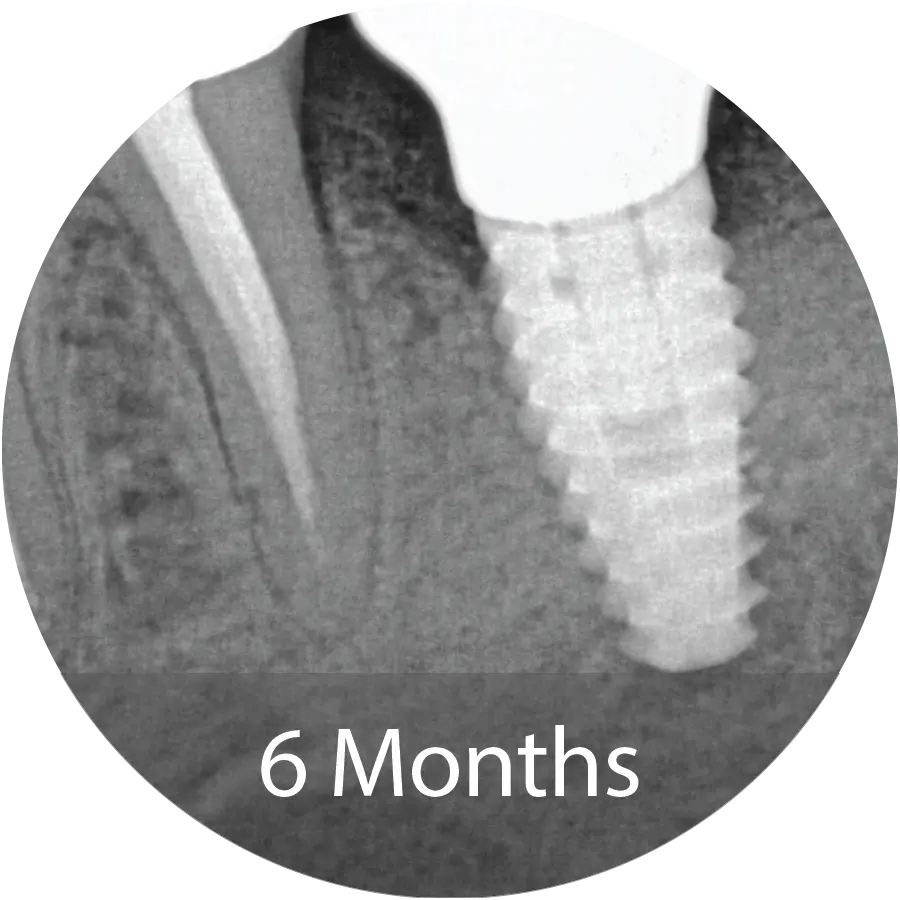

67-year-old male presented for extraction of tooth #18. An Alveolar ridge preservation procedure was performed utilizing INDUCE Oi-9® Fiber Matrix covered with an amnion chorion membrane.

Evaluation of the bone core with micro-CT and histological staining demonstrated mineralized tissue consistent with new bone, surrounded by loose trabecular structures. Implant placement was performed at 6 months following grafting.